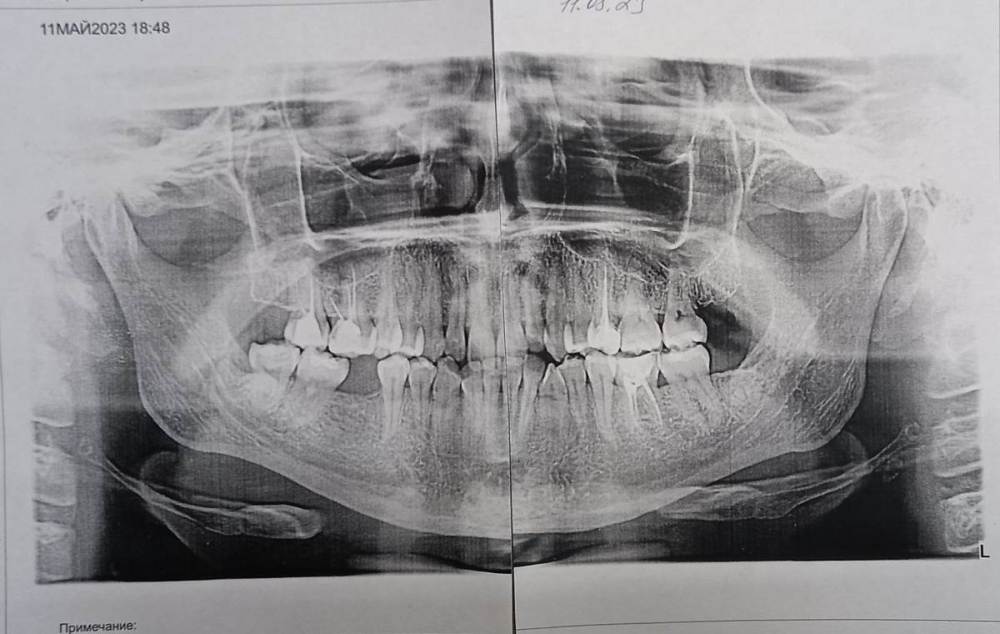

Mariaduya Опубликовано 5 июля, 2023 Поделиться Опубликовано 5 июля, 2023 (изменено) Здравствуйте. У меня сложная ситуация, боли в челюсти практически 1.5 года. Врачи не видят проблем, уже не знаю куда обратиться. Хронология. 1. В ноябре 2021 начал слегка болеть 1.6 зуб. В стоматологии мне его сразу начали депульпировать, без снимка. В ходе лечения не болел, как запломбировали каналы, постепенно появилась ноющая, постоянная боль. Я обратилась снова, сказали, что на зубе есть хроническое воспаление и ввели антибиотик туда при помощи электрофареза. Среагировал 2.5 зуб с другой стороны, и тоже начал постоянно болеть, он был депульпирован давно, но в нем развился большой кариес. 2. Мне начали их перелечивать. 1.6. не получилось пройти канал, залили резодентом, 2.5 просто переличили. 3. Боль все ещё осталась, уже в двух зубах. Врачи ничего не знают, отправили к неврологу, ЛОРУ и т.д. 4. Обошла неврологов, лоров, делала мрт, кт с контрастом головы, пазух носа, все ок. Невролог выписывает финлепсин, не помог. 5. Делала в частной клинике кт зубов, без описания, ещё не знала, что оно нужно, врач посмотрела и сказала, что видит небольшое, хроническое воспаление на 1.6 зубе и все, а так она не знает. 6. И так 1.5 года никто не знает, что со мной. Боль 1.6 и 2.5 зубы, начинают и нижние зубы болеть, уже и ухо болит. После орви болит все очень сильно, что хочется уже не просыпаться. Удалять их говорят не показаний, вдруг боль останется. Снимки в хронологии выкладываю. Есть ли на них воспаление 1.6 зуба, 2.5 зубов, есть ли них кисты свищи и все что угодно, что аномально и может вызывать боль. Может что-то с надкостницой, или суставами. Все что у меня есть - интернет, так как живу я очень далеко от нормального города и доступна только городская поликлиника, где врачи говорят, что это неврология, а невролог говорит наоборот. Сами зубы болят странно, по очереди. Если болит неделю 1.6 зуб, то 2.5 не болит и так наоборот. Вместе они не болят. Ещё странное то, что они практически симметричны друг другу по расположению. Изменено 5 июля, 2023 пользователем Mariaduya Ссылка на комментарий

Carioznik Опубликовано 5 июля, 2023 Поделиться Опубликовано 5 июля, 2023 Здравствуйте, 27 зуб надо внимательнее посмотреть, возможно там пульпит (но это неточно "бумажные " снимки малоинформативны). Скиньте лучше КТ или хотя бы ОПТГ но в электронном формате(а не фото распечатки на бумаге) Ссылка на комментарий

Mariaduya Опубликовано 8 июля, 2023 Автор Поделиться Опубликовано 8 июля, 2023 Уже после лечения 25 и 16 зубов, он отличается от современного только тем, что перелечивали ещё нижний 6 зуб. А так, такая же ситуация, как и на сегодня. Ссылка на комментарий

Carioznik Опубликовано 13 июля, 2023 Поделиться Опубликовано 13 июля, 2023 по этому старому КТ: на 16 - есть пропущенный канал, от этого, на одном из корней - есть небольшой воспалительный процесс (на тот момент). "Само не заживет", будет только расти, может, на сегодняшний момент - уже стал большой). Но жалобы в таких случаях обычно другие. Делайте новое КТ (по старому только гадать...) и снова, очный осмотр стоматолога, явно понадобится. 1 Ссылка на комментарий